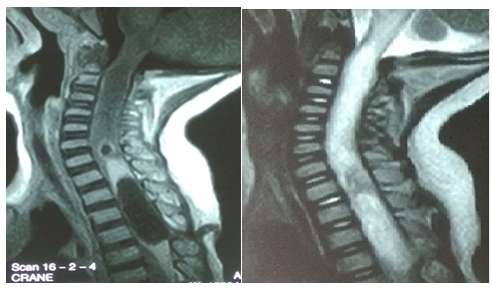

Figure 1 An abnormality of lesional signal, hypo-intense in T1, hyper-intense in T2, with a small zone in cockade with a hypo-intense center at the height of C6-C7, a part strongly enhanced opposite T1, a fusiform part 31x11, 8 mm just below. A linear fistula was seen causing the collected lesion to communicate with the skin.

It is a 15-month-old infant of Mauritanian nationality, with a history of unprotected neonatal infection, received in our neurological clinic for motor deficiency of the two lower limbs. His psychomotor development was normal. The symptomatology evolved for about 4months, with the occurrence of a fever, irritability and a dorsal kyphosis. In view of these manifestations, the infant was brought to the local health center for treatment, where a non-documented treatment has been instituted for a period of 10days. After 10days of treatment, the patient presented progressively over 20days a motor deficit of the lower limbs preceded by a functional impotence of the lower limbs causing an impossibility of the walking and the seated station, without context of acute retention of urine or constipation. This is what motivated the parents to consult again in another health center in Nouakchott where the patient was hospitalized for 5days and left without improvement of his clinical picture. Finally, he will be referred to the FANN Neurology Clinic in Dakar for specialized care. It should be noted that the parents of the infant had detected a dorsal cutaneous swelling during his neonatal period, but they had thought that it was an innocent lesion that did not need further investigation (of little clinical importance). The clinical examination found a good state of hydration, hyperthermia at 38.5°C. The infant was conscious with good preservation of superior functions. However, he had a spastic paraplegia with a muscular force rated at 0/5 on the two lower limbs, osteo-tendinous reflexes were sharp at the two lower limbs, poly kinetic and diffuse with an epileptoid trepidation of the feet, plantar reflexes were in extension, the neck was supple. On the other hand, tone, muscle strength and osteo-tendinous reflex were normal to the upper limbs. There were no signs of meningeal irritation. At the level of the musculoskeletal system, a kyphosis of the dorsal spine was noted with a slight hyper chromic swelling surrounded by a pilosity with respect to the T3-T4 dermatomes, suggesting a dermal sinus (Figure 1). The rest of the clinical examination was normal. The hypotheses of a compressive or non-compressive myelopathy associated with dysraphia were mentioned. The medullar MRI performed showed an edema of the cervico-dorsal marrow as well as the bulbar junction, with lesional signal abnormality, hypo-intense T1, hyper-intense T2, heterogeneous enhancement, with a small area In a cockade with a hypo-intense center at the height of C6-C7, a part strongly raised facing T1 and a fusi form part of 31x11,8mm just below. A linear fistula was seen, communicating the collected lesion to the skin (Figure 2). The diagnosis of intramedullary abscess was retained. The haematological assessment found a leukocytosis at 19000/mm3 and the sedimentation rate was high. A neurosurgical procedure was performed and confirmed the existence of the dermal sinus, communicating the skin to the medullary space through a cord (Figure 3). Partial Laminectomy was performed with drainage and lavage of the cavity (Figure 4), but also a resection of the sinus. The cytobacteriological examination of pus isolated Staphylococcus aureus. Prior to pus culture, treatment consisted of broad spectrum antibiotic therapy with Ceftriaxone, Metronidazole and Gentamycin. And after the isolation of the germ, the infant was put on Vancomycin and Chloramphenicol. Evolution was satisfactory with partial recovery of muscle strength.